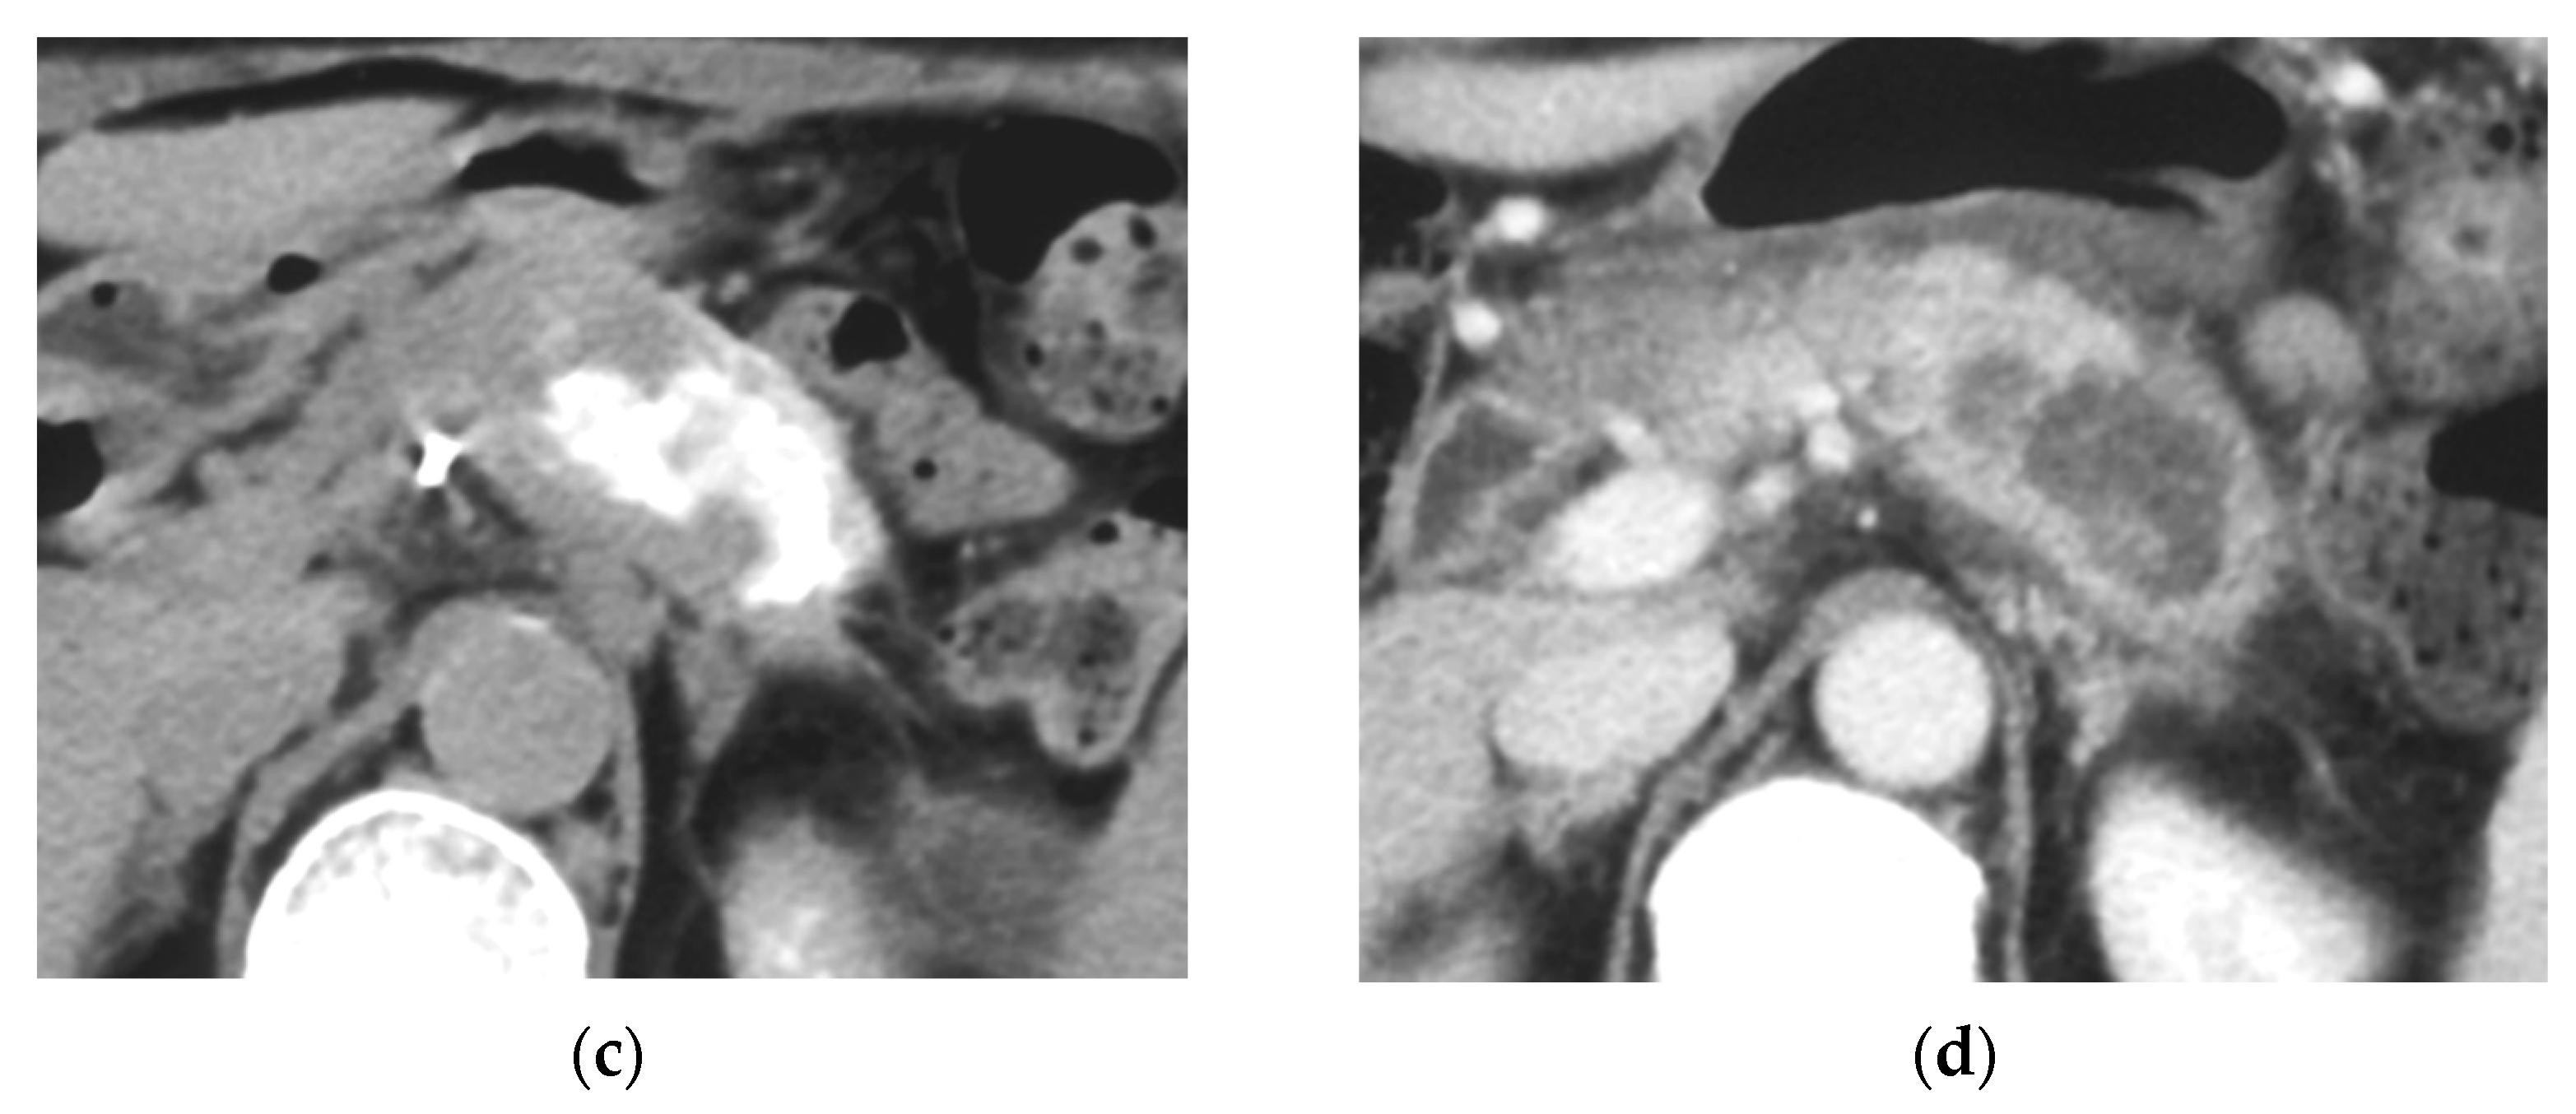

Identifying Supplying Arteries to Pancreatic Cancer

Method of Arterial Administration of Anticancer Agents

3.5. Tumor Response